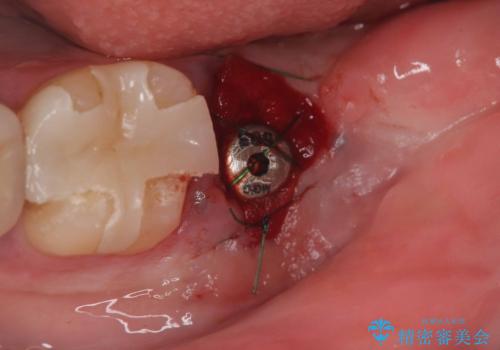

保存は困難と判断し、左下7番は抜歯即時インプラントによる治療を行いました。

抜歯と同時にインプラントを埋入するため、歯茎を切開する必要がなく、術後の痛みが出にくい治療方法です。

手術は1回で完了し、被せ物を装着するまでの治療期間も約3か月と、身体的・時間的な負担を抑えることができます。